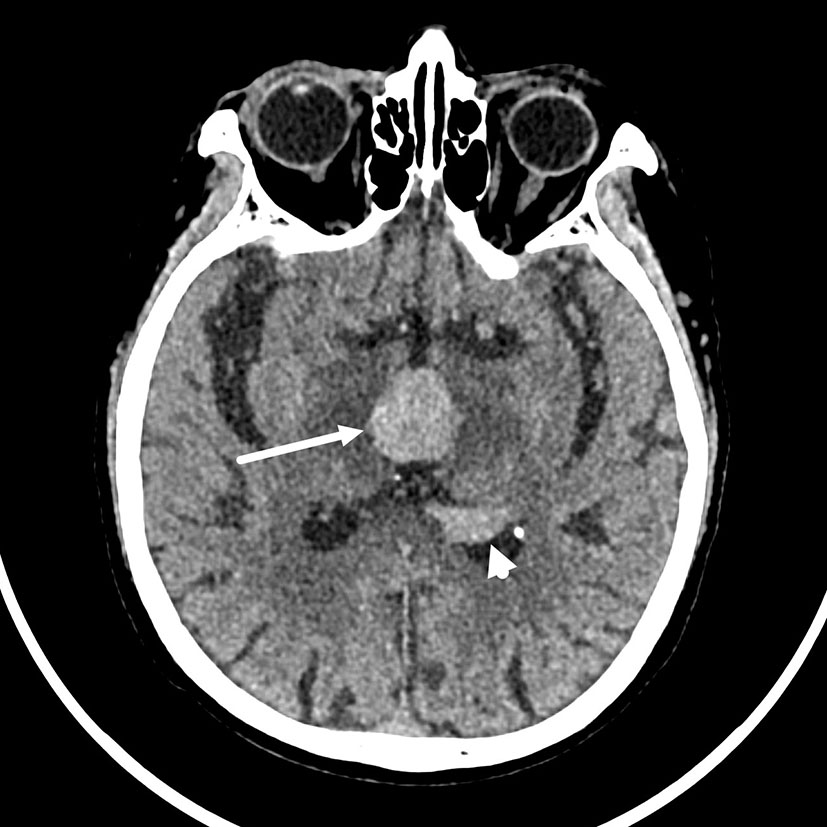

The brain computed tomography (CT) disclosed three solid masses with slight hyper-attenuation, non-calcification, and non-cystic components. The biggest one was located in the third ventricle and the others were located in the body and posterior horn of the left lateral ventricle (Figure 1), MRI showed multifocal solid lesions in the same regions. They were slightly hypointense on T1WI and isointense to slightly hypointense on T2WI and T2WI dark-fluid images. While on diffusion-weighted imaging (DWI), the third ventricular lesion was hypointense, and the lateral ventricular lesion was slightly hyperintense, both of them with low apparent diffusion coefficient (ADC) values, all suggesting diffusion restricted. Post-enhanced, the ventricular lesions were significantly enhanced. Furthermore, parenchyma around the third ventricle displayed swelling and hyperintense on T2WI. It did not cause ventricular expansion and hydrocephalus above the lesions (Figures 2A–F). He was diagnosed with intraventricular malignancy and based on his history of prostate cancer, the possibility of metastasis was considered clinically.

Figure 1

Non-contrast computed tomography (CT) shows that the masses with slight hyper-attenuation were in the third ventricle (the tumor size: 22 mm × 22 mm × 15 mm, CT value: 47HU) (arrow), in the body (not shown) and posterior horn (arrowhead) of the left lateral ventricle.